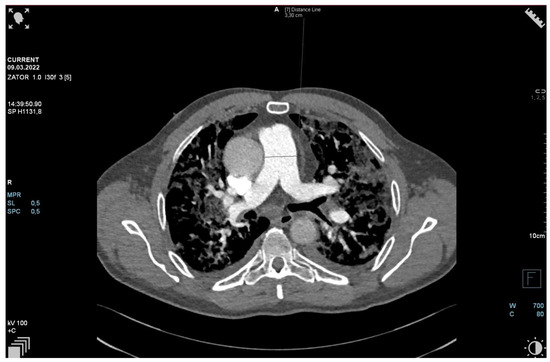

The patient required oxygen therapy, and initially, due to a lack of diagnosis, he received empirically broad-spectrum antibiotics (meropenem, linezolide). On laboratory testing, a further increase in inflammatory and coagulation biomarkers (CRP, ferritin, interleukin-6, D-Dimer, fibrinogen) was observed. Blood cultures as well as a respiratory PCR multitest were negative. Due to the dynamic increase in D-dimers and the elevation of cardiac biomarkers (BNP, NT-proBNP) along with dyspnea, an angio-CT was performed. It excluded pulmonary embolism, but it revealed widening of the pulmonary trunk and pulmonary arteries, as well as alveolar compaction in both lungs and bilateral pleural effusion. Pulmonary edema was diagnosed (Figure 2, Figure 3 and Figure 4).

Figure 2.

Angio-CT scan.

Figure 3.

Figure 4.